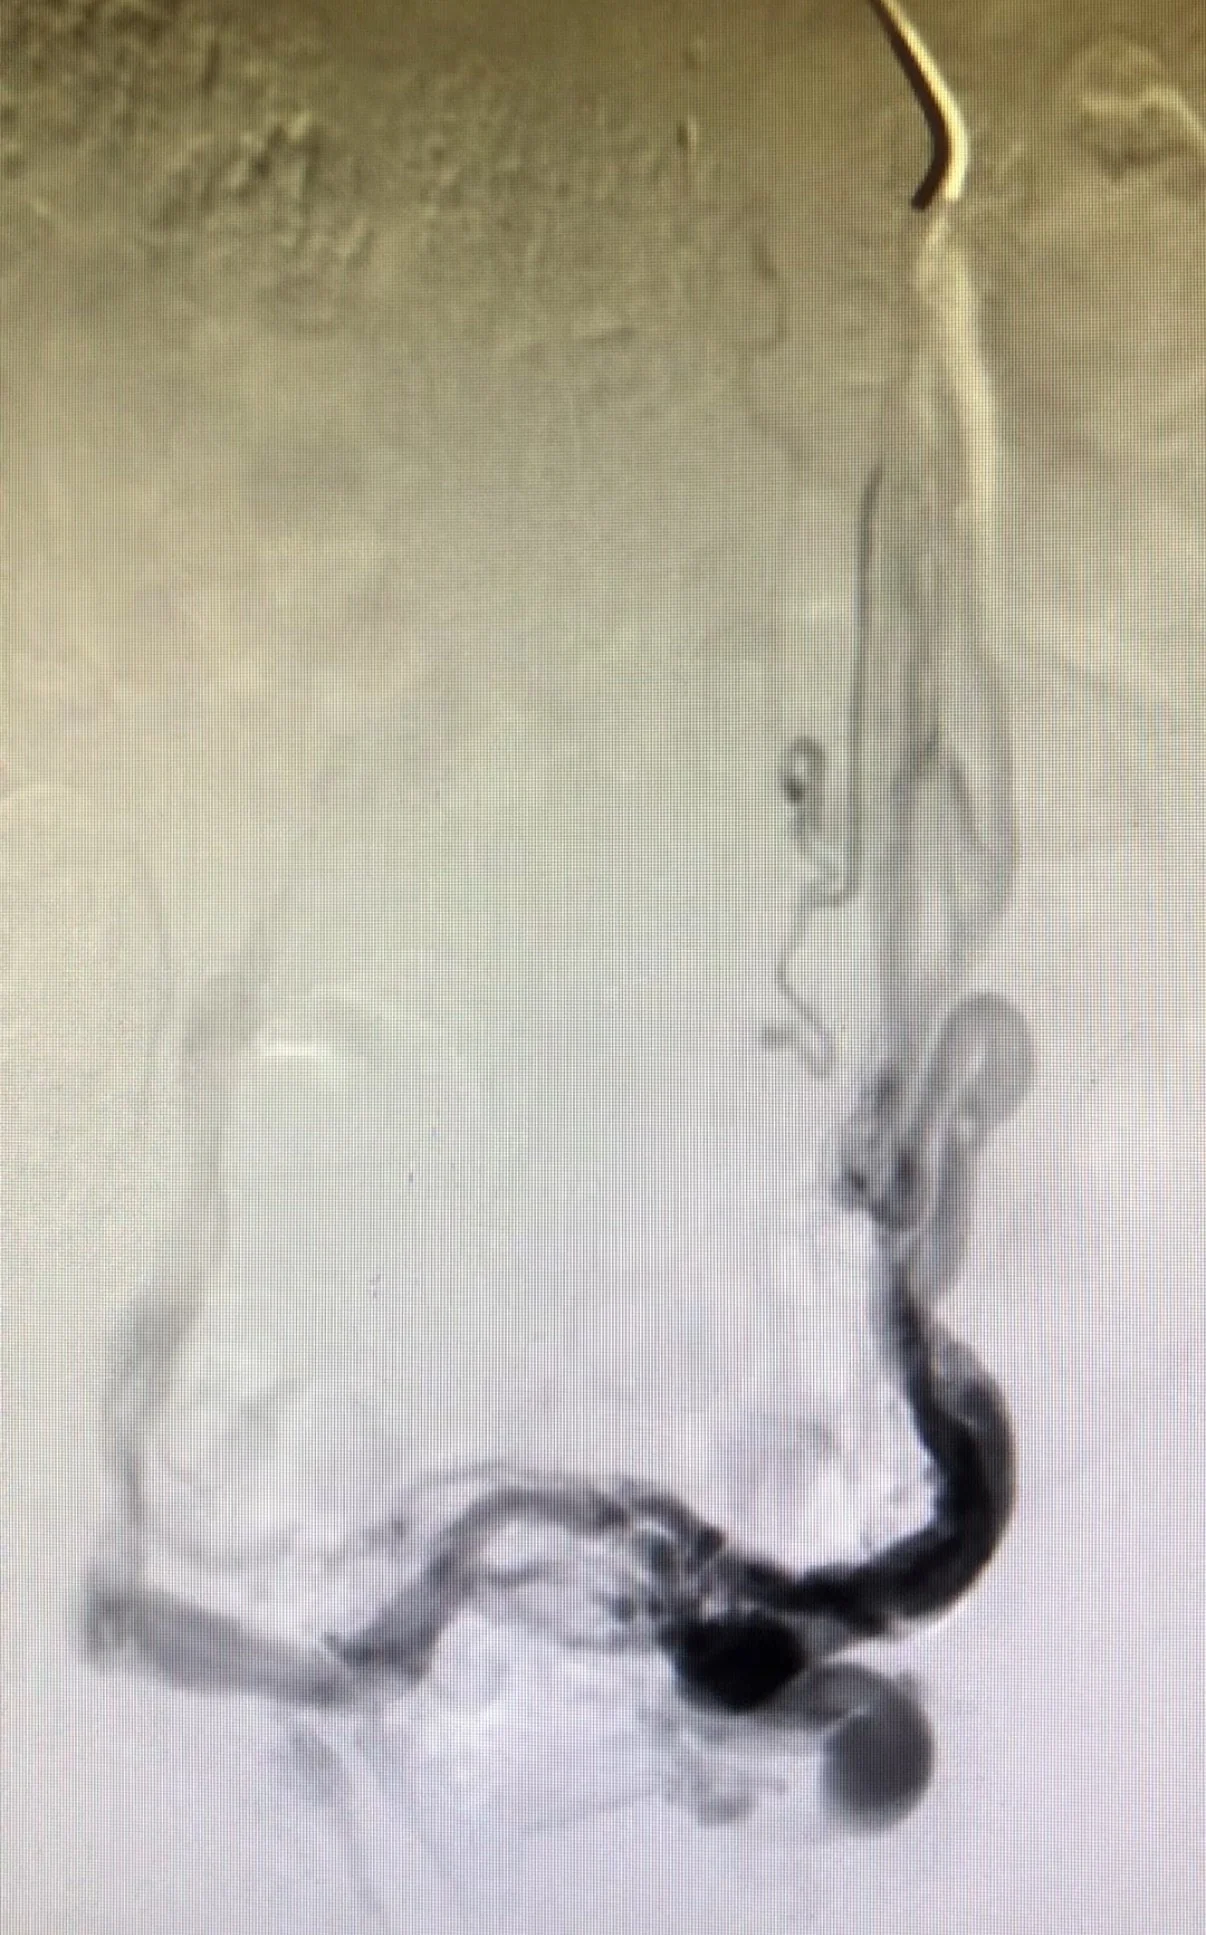

2. Nutcracker Syndrome: compression and obstruction of the left renal vein causing venous blood flow reversal into the pelvis via left ovarian vein.

In evaluating PCS secondary to pelvic venous insufficiency, it is essential to assess for underlying contributors such as May-Thurner and Nutcracker syndromes. These vascular compressive disorders may be the primary drivers of venous reflux in the left ovarian and bilateral iliac veins. Initiating treatment for PCS without identifying and addressing these causative lesions can compromise outcomes and lead to persistent or worsening symptoms. Similarly, hysterectomy, oophorectomy, or other pelvic procedures involving resection of associated venous structures of the pelvic organs may significantly exacerbate symptoms by eliminating the natural decompressive function of pelvic varicosities.

CT | MR | US | Venogram with IVUS